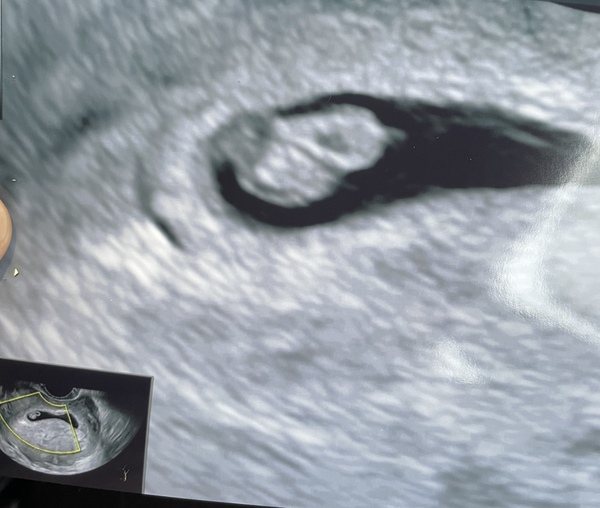

Had a couple of days of lights brown spotting so moved my private scan forward from Sunday to today. Fortunately, everything is ok and was able to see the heartbeat ❤️ Baby is measuring 6w2d.

Congratulations @Motherofpugs - what a lovely scan! I bet you feel so relieved!

Congratulations @Motherofpugs on your scan. I’ve had some spotting too. I spotted throughout the first trimester when I had my son so am trying not to be concerned by it.